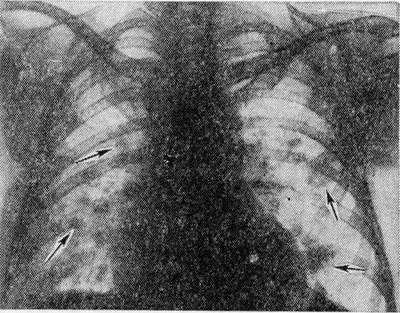

Рис. 2. Рентгенограмма грудной клетки больного с синдромом Леффлера: множественные двусторонние инфильтраты в легких (указаны стрелками).

Наиболее типичным рентгенол, проявлением Л. с. является тень одиночного инфильтрата, расположенного в любом отделе легкого, небольшой или средней интенсивности и, как правило, ее размеры 3—4 см в диаметре. Форма тени обычно неправильная, очертания нечеткие (рис. 1). Окружающий легочный рисунок усилен в связи с местной гиперемией. В большинстве случаев тень соответствующего корня легкого слегка расширена, структурна. При многопроекционном исследовании удается установить, что инфильтрат располагается чаще в плащевидном слое легкого. В связи с этим нередко можно выявить утолщение плевры, расположенной в непосредственной близости к инфильтрату. Характерным для динамики инфильтрата при Л. с. является его исчезновение через 1 — 3 дня после выявления; на месте бывшего инфильтрата в течение нескольких дней остается постепенно уменьшающееся усиление легочного рисунка. Такая быстрая динамика дала основание назвать эти инфильтраты летучими. Реже при Л. с. встречаются инфильтраты, принимающие форму анатомических структур — сегментов, долей, и множественные инфильтраты, к-рые иногда могут быть двусторонними (рис. 2). Быстрое исчезновение является типичным для всех видов инфильтратов при Л. с. В относительно редких случаях инфильтраты могут рецидивировать. В отдельных случаях при наличии крупных инфильтратов можно обнаружить небольшой транссудат в плевральной полости, к-рый рассасывается в течение нескольких дней.